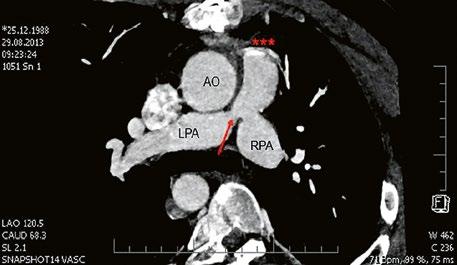

Obr. 45.40 CT angiografie, 8mm stenóza a deformace levé větve plicnice (šipka) po spojkové operaci podle BlalockaTaussigové v dětství LPA – levá větev plicnice, PA – kmen plicnice, RPA – pravá větev plicnice

Obr. 45.41 Uzávěr levé větve plicnice jako následek provedené spojky podle BlalockaTaussigové v dětství, CT angiografie